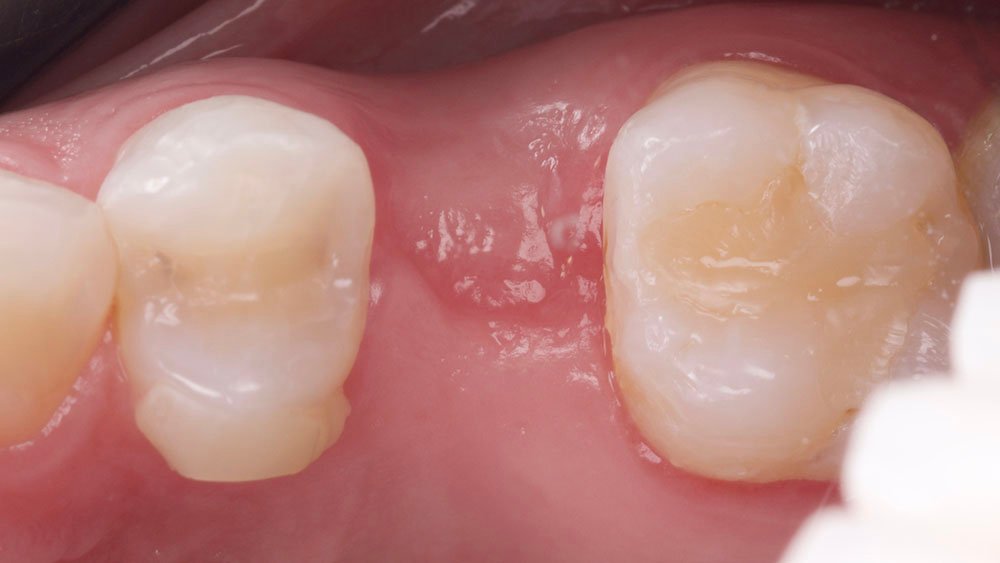

Durante a anamnese, a paciente apresentou um bom estado de saúde geral e não relatou nenhum dado médico relevante que impossibilitasse o tratamento. No exame físico intraoral, observou uma boa condição de saúde bucal, notando-se apenas a ausência do elemento 15 com uma depressão óssea no vestibular. Dessa forma, objetivou-se um plano de tratamento baseado na utilização da técnica de rolo modificada e colocação de dente provisório.

A técnica de rolo modificada aborda uma quantidade maior de tecido conjuntivo que poderia ser enrolado, minimizando a exposição do osso e preservando o epitélio sobre ele, contribuindo com uma técnica mais confortável aos pacientes2.

Essa técnica é indicada para correção de tecidos moles horizontais leves à moderados5. A sua vantagem sobre a técnica de rolo tradicional inclui o máximo de quantidade de tecido conjuntivo que pode ser enrolado na região bucal, minimizando a quantidade de osso exposto, preservando o epitélio sobre ele e assim, minimizando o desconforto ao paciente3.